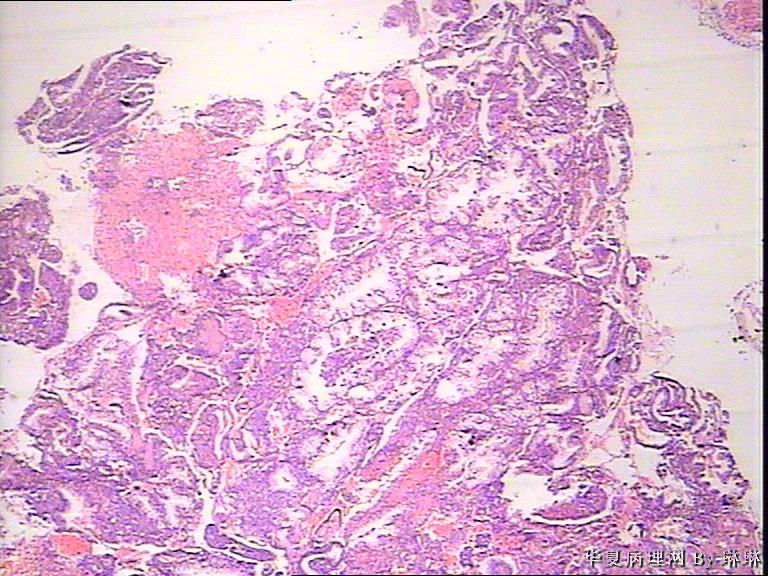

患者女性,38岁,月经量多4个月,曾服用止血药物,无其他病史。

• 子宫内膜,请教图2

图2

开始临床没有提供怀孕的病史,后来我们有咨询临床科室,大夫还是说没有用药、月经正常,刚过了经期,月经量多,这次月经持续时间长入院。所以我们开始排除了高度分泌的A-S反应,看到腺体增生呈乳头状,还有异型性,而且镜下部分子宫内膜还有增生期改变的,不完全是高度分泌的。再三考虑后还是要求临床查了血HCG,结果显示HCG370多。最后我们发了单纯性增生伴高度分泌。

腺体呈高度分泌反应,我们必须结合病史,考虑是否药源性反应,或持续黄体期子宫内膜.

晚泌期宫内膜,并见A-S现象

复杂性增生伴分泌反应